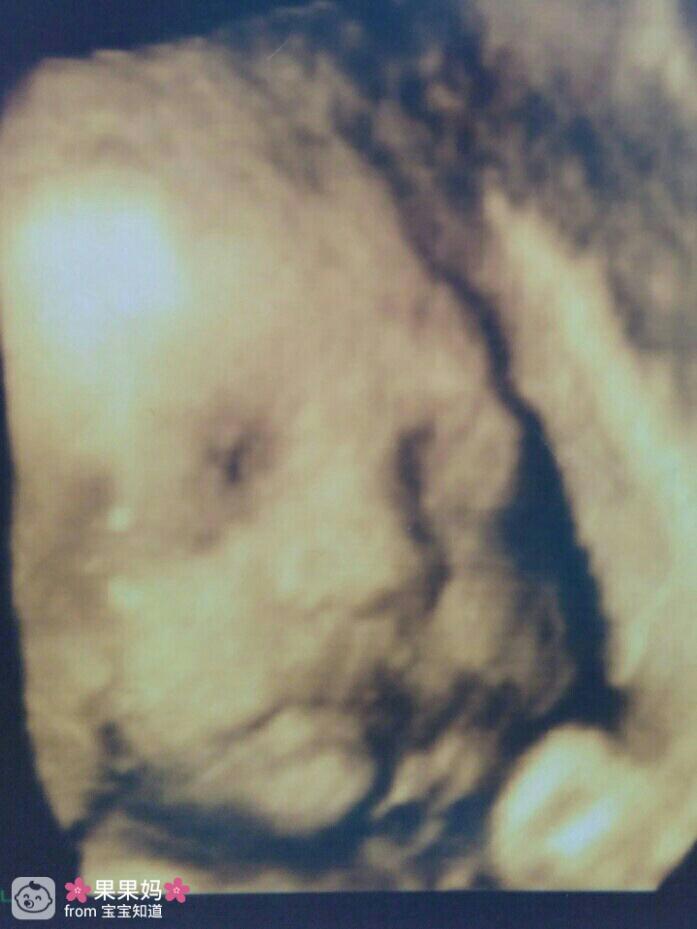

,医生量了一下肚子,说宝宝7-8斤,问顺还是刨,老公和婆婆都建议刨,我是想顺产的,当医生说顺产会发生各种菜耻危险时我犹豫了,我问医生刨妇产一定安全吗?医生说刨妇产有其他危险,医生这么说后,就坚定了自己顺产的意念!抽血,B超,心电图,一切检查顺利后开始幸福而漫长的等待!

因为经历了第一次的内检,不想做第二次的内检,记得看过其他帖子说间隔时间短疼的时间瓣夕长就是快生了,就想着等到那个时间在做,医生和婆婆看我疼的好像要生了催我去做内检,两点多内检两指半,OMG!婆婆说要不刨吧,怕我坚持不住,我依然说顺!下午4点多进产房,实在太疼了,坐着轮椅哭着进去的,到产房后内检3指半(产房的医生内检舒服多了),医生说你这才3指半有那么疼吗?不想理她,冷血动物!催产素,破水,等待!下午6点多内检7指,医生建议用无痛,怕生的时候悟乡狗没劲,准备无痛,麻药,仿生,红牛,士力架,氧气,准备生产,因为宝宝头大,而且是脸朝上的,所以用了产钳,侧切,晚上9点45分,小公主出生,体重4500克,身高53厘米!